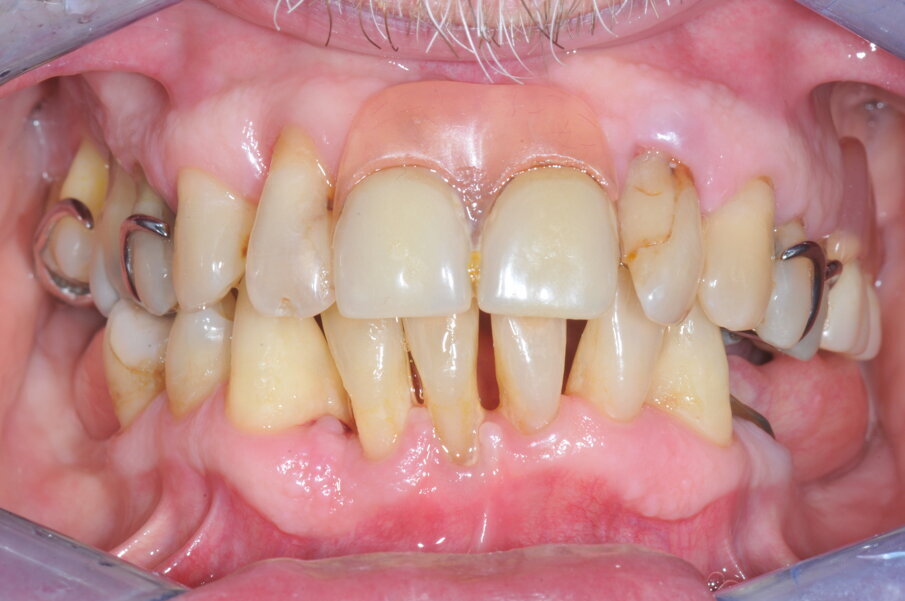

Il paziente si è presentato alla nostra attenzione a causa di un grave inestetismo legato a una protesi parziale rimovibile superiore incongrua. Il paziente lamentava inoltre mobilità dentale generalizzata e sanguinamento gengivale. In anamnesi non sono state segnalate controindicazioni a interventi chirurgici, mentre l’analisi clinica e radiologica ha evidenziato una dentatura terminale caratterizzata da parodontite severa e cronica, perdita ossea orizzontale, otturazioni incongrue ed elementi dentari malposizionati (Figg. 1a, 1b). La volontà del paziente era realizzare una riabilitazione fissa superiore possibilmente senza interventi di rigenerazione ossea a causa dell’incremento in termini di costi economici, biologici, e di tempo. Il piano di trattamento proposto prevedeva una riabilitazione protesica fissa avvitata su 4 impianti mono-componente a carico immediato post-estrattiva, con un approccio chirurgico flapless e una progettazione interamente digitale.

Fig. 1a_Situazione clinica iniziale.

Fig. 1b_Situazione clinica iniziale.